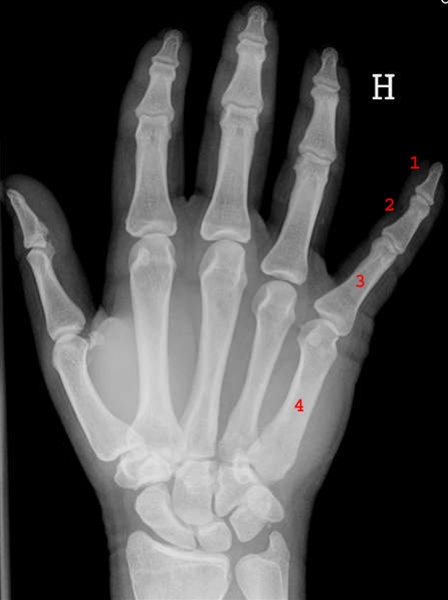

Mellemhåndsknoglerne, (metakarperne), forbinder håndroden med de fem fingre. Tommelen kaldes 1. finger og mellemhåndsknoglen 1. metacarp, og det gælder også de øvrige fingre, således at lillefingeren kaldes 5. finger og mellemhåndsknoglen 5. metacarp.

En mellemhåndsknogle består af to ledhoveder og et langt skaft. Mellemhåndsknogler (nr. 4 på billedet) danner led med fingerknoglerne i den ene ende og med håndroden i den anden ende.